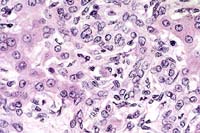

Case 22-1. Liver. Proliferating lumenless bile ductule epithelium and fibroblasts in the portal area are infiltrating the limiting plate of the lobules, with a few neutrophils. An individual ductule cell has eccentric cytoplasm containing a microsporidial cyst with 0.5-1.0µ spores (Enterocytozoon bieneusi). 40X

Contributor's Diagnosis and Comments: Liver: Nonsuppurative cholangiohepatitis with marked proliferation of bile ductules, bridging portal fibrosis and extrusion of individual biliary epithelial cells containing microsporidial organisms.

Infection with E. bieneusi has been diagnosed in three species of macaques (Macaca mulatta, M. cyclopis and M. nemestrina) and the organism may be identified in both immunocompetent and immunodeficient individuals. This organism is virtually indistinguishable at the morphologic and genetic level from that identified in human AIDS patients. In immunodeficient animals, the organism is most commonly found in the gall bladder and common bile duct and less frequently in the small intestine and liver. The characteristic findings in the gall bladder and common bile duct are a nonsuppurative and proliferative cholecystitis and choledochitis. As seen in this case, extrusion of individual biliary epithelial cells is often evident. These cells contain mature spores which are visible as 1.0-1.5 um diameter negative images or lightly basophilic bodies on routine H&E stained sections. In our colony, the triad of bridging portal fibrosis, nodular lymphocytic infiltrates and marked bile duct and ductular hyperplasia within the hepatic parenchyma has been found exclusively in association with E. bieneusi infection. In these cases, the organism is found most commonly in intralobular hepatic ducts and less frequently within proliferating bile ductules.

AFIP Diagnosis: Liver: Hepatitis, portal and periportal, bridging, lymphoplasmacytic and neutrophilic, chronic, with biliary hyperplasia, multifocal periportal hepatocellular necrosis, and rare extruded individual biliary epithelial cells containing microsporidial organisms, Rhesus monkey (Macaca mulatta), primate.